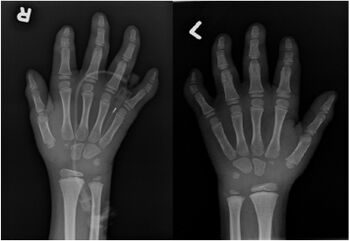

X-ray hands showed deformity of the middle phalanx of the 5th finger bilaterally with the lateral aspect of the phalanx being shorter than the medial aspect (PIGL)[8][9]